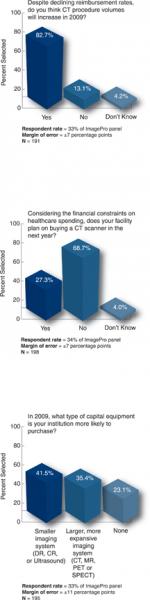

Buyer behavior and purchasing patterns evolve over time, particularly for capital equipment and information technology. What was important in the purchasing decision five or 10 years ago may not be today, as environmental, operational and technological changes impact the decision-making process.